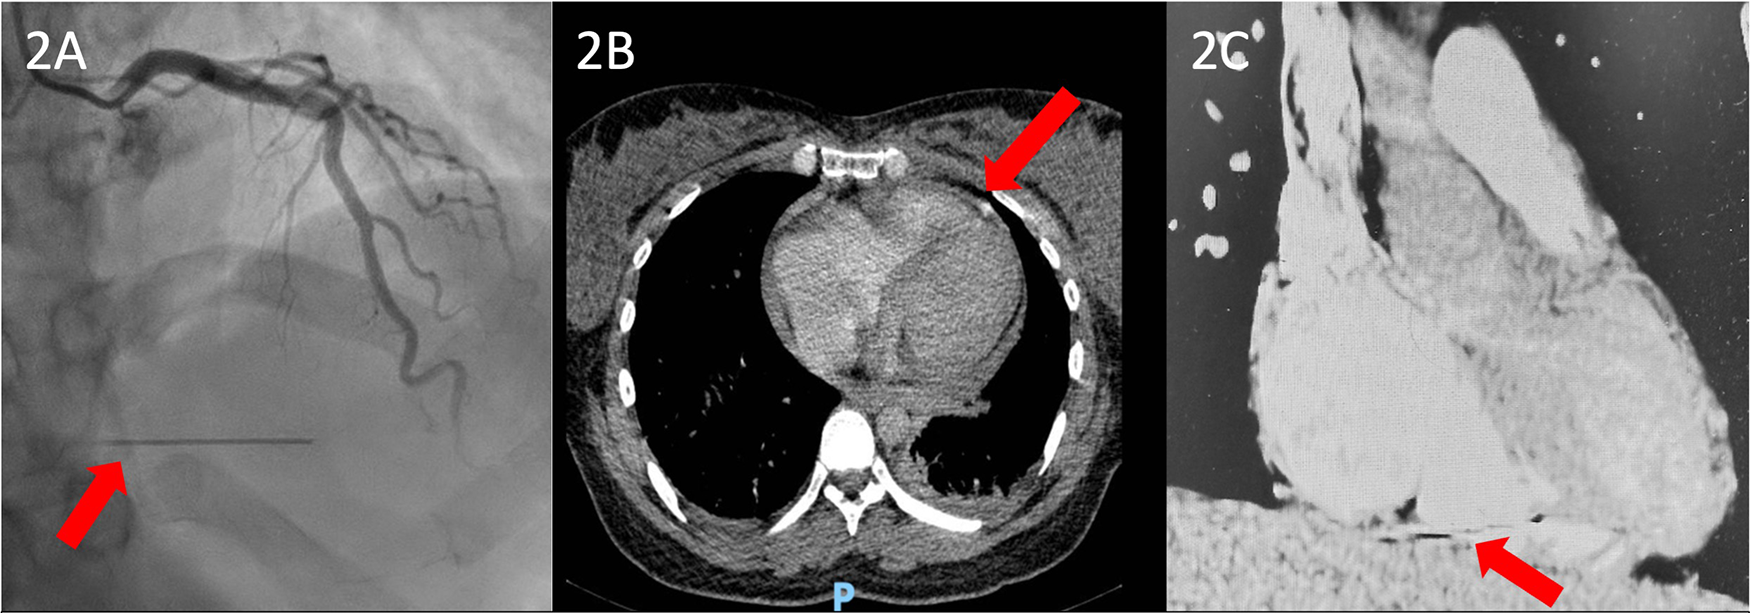

Given the favorable evolution of the patient and her fetus, the good tolerance of the tricuspid insufficiency, and the slight reduction of the tricuspid and subvalvular vegetations, with no signs and symptoms of heart failure or other complications of the infectious endocarditis (IE), the patient was discharged, with the recommendation of a weekly echocardiographic evaluation. One month after an uneventful delivery, the patient was admitted to our hospital for the completion of the preoperative protocol. Upon admission, various tests were performed, including an electrocardiogram, coronary angiography, echocardiography, and a chest CT scan. Blood cultures were negative upon admission. The echocardiographic evaluation showed normal left ventricular (LV) function and a thickened tricuspid valve, particularly at the level of the septal cusp on the atrial side, where a filamentous hyperechoic mass measuring only 6 mm × 2 mm was observed, reflecting a favorable response, along with severe tricuspid regurgitation. Coronary angiography showed normal coronary arteries (Figure 2A). However, during angiography, a needle was discovered in the inferior wall of the right ventricle, which was confirmed by the CT scan.

Figure 2

(A) Preoperative coronary angiography showing an unusual hyperdense radiopaque foreign body likely embedded within the myocardial wall, with synchronous motion with the cardiac cycle (red arrow). (B) Coronal CT scan view and (C) sagittal CT scan view showing a hyperdense needle-like foreign body containing internal lumina entrapped in the right ventricular myocardial wall.

The initial failure to detect the foreign body during the patient's first hospitalization can be explained by a combination of factors, including suboptimal imaging angles, artifact misinterpretation, and diagnostic limitations imposed by the ongoing pregnancy, which restricted the use of comprehensive radiological tools. It is also plausible that the metallic fragment was mobile and subsequently migrated, eventually embedding itself deeper into the right ventricular myocardium, which further contributed to its late visualization on echocardiography. A preoperative computed tomography angiography (CTA) performed upon readmission clearly identified the foreign body and confirmed its anatomical position, with one end of the fragment located in the cavity, and the other outside of the cavity (Figures 2B,C). Importantly, there were no signs of pulmonary embolism, and the patient remained normoxemic throughout both the perioperative and postoperative periods.